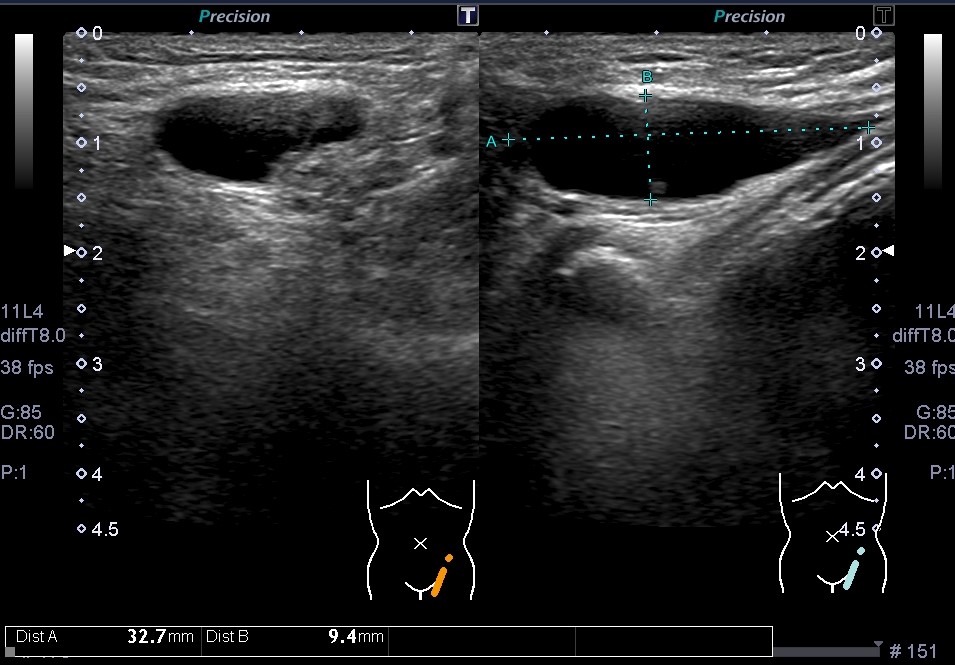

• 鼠径部組織のリアルタイム画像を見るための超音波検査